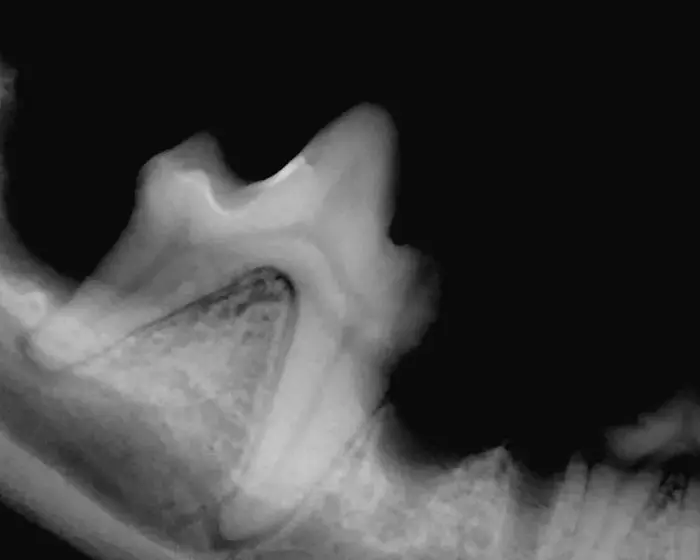

Røntgenfotografering af tænder

Tandrøntgen er et uundværligt hjælpemiddel i daglig dyrlægepraksis.

Fra billedet er taget går få sekunder før det vises på computeren.

Via tandrøntgen ses eventuelle rod problemer, som ikke ville være opdaget ved blot at se på selve tanden.